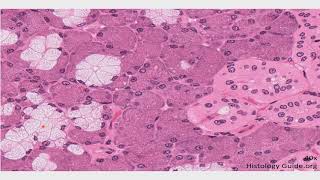

hepatocitos que es el espacio perisinusoidal tenemos otro espacio que se encuentra en los extremos de esta estructura que más adelante vemos que la vamos a denominar lobulo hepático que se llama espacio portal en este espacio portal donde nosotros vamos a encontrar a los elementos de la triada portal y esto a groso modo es todo lo que podemos encontrar dentro del hepatocito a continuación Entonces vamos a estudiar cada una de estas estructuras Empezando por el parénquima hepático como ustedes pueden observar acá pues los hepatocitos están unidos unos con otros formando cordones y se denominan de hecho

vena centrolobulillar que va a estar rodeado por los cordones hepáticos formados por hepatocitos sí cada cordón hepático va a estar separado uno uno de otro por medio de estos sinusoides hepáticos Recuerden que estos sinusoides están tapizados por endotelio y son el sitio donde confluyen o se une o se mezcla la sangre venosa con la sangre arterial en la periferia de este lobulillo clásico es decir en todos los ángulos en todo el perímetro en todos los bordes del lobulillo vamos a encontrar nosotros a estas estructuras de acá Este espacio de aquí se conoce como espacio portal

es una célula poliédrica de más o menos una forma hexagonal que forma aproximadamente el 80% de la población celular total del parenquima hepático visto desde el microscopio los hepatocitos tienen un núcleo inmenso extremadamente grande por lo general central a veces los citos eh más más grandes o más maduros son incluso binucleados pero tienen un núcleo redondo siempre ubicado en el centro el citoplasma del hepatocito pues está ocupado de millones de organelas porque son células metabólicamente muy pero muy activas Como por ejemplo podemos encontrar Aproximadamente en el interior de cada hepatocito de 800 a 1000 mitocondrias